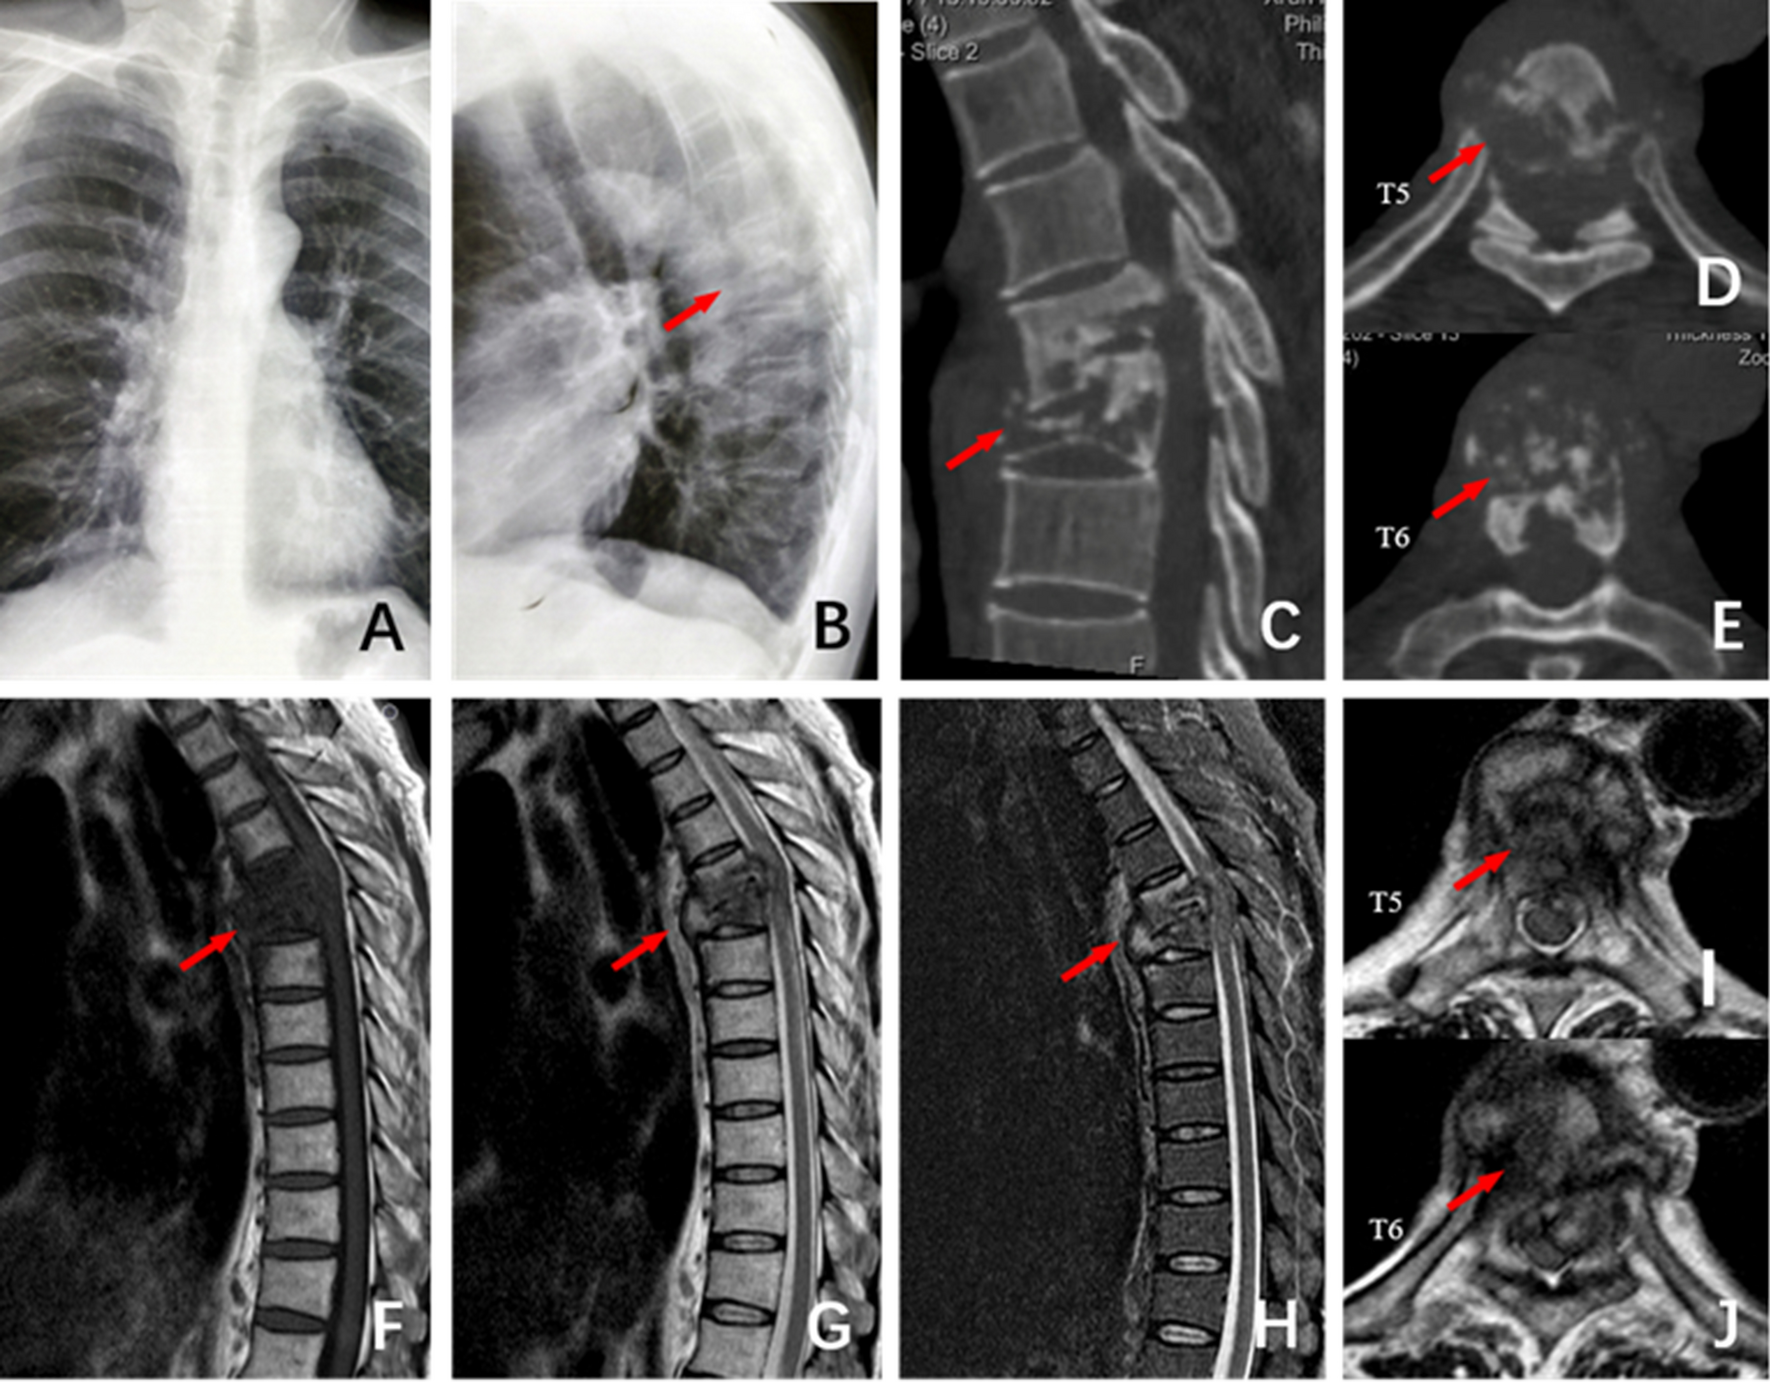

Figure 1

The patient, male, 51 years old, T5 ~ T6 spinal tuberculosis secondary to kyphosis deformity. (A) and (B) The frontal and lateral X-ray films before surgery showed vertebral destruction of T5 ~ T6 and Cobb Angle of 40°. (C–E) Preoperative CT showed severe damage to the anterior column of the T5 ~ T6 vertebral body and normal posterior column. (F–J): Preoperative MRI showed vertebral destruction of T5 ~ T6 and obvious compression of the spinal cord.